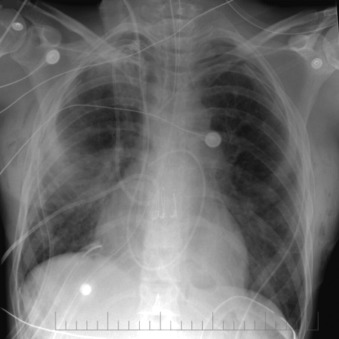

Central Venous Lines ( Figs. 22-1 to 22-13 )

To avoid mechanical irritation (from the catheter tip) and chemical irritation (from infusate) of the right atrium, the catheter tip of a central venous line should be further than the junction of the internal jugular vein and subclavian veins (near the level of the first thoracic rib). In addition, the tip should not be further in than the junction of the superior vena cava and right atrium. Central venous catheters that are intended to record central venous pressure should lie distal to the last venous valves (in the subclavian and internal jugular veins, 2.5 cm proximal to the beginning of the brachiocephalic vein) and before the right atrium. The ideal position of the tip of a peripherally inserted central catheter (PICC) line is in the distal superior vena cava.